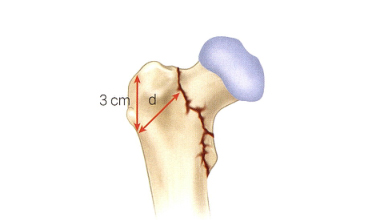

Оптимальное лечение «нестабильных» межвертельных переломов бедренной кости остается спорным. В недавней литературе предполагается, что переломы А2 АО/ОТА из-за значительного заднемедиального измельчения можно лечить с помощью экстрамедуллярных или интрамедуллярных устройств, но степень успеха неопределенна. Напротив, переломы типа А3 с расширением латеральной стенки требуют интрамедуллярной фиксации. Несколько исследований показали, что для успешного лечения межвертельных переломов экстрамедуллярными имплантатами необходима неповрежденная латеральная стенка. Hsu и соавт. продемонстрировали, что толщина боковой стенки менее 20,5 мм является надежным предиктором послеоперационного перелома боковой стенки. В последнем 14-м издании «Ортопедической хирургии Кэмпбелла» также четко говорится: «При нестабильных межвертельных переломах (переломы А3 и некоторые переломы А2) лучшим лечением является использование интрамедуллярной фиксации гвоздями. (п2635)

Примечание: Диаграмма толщины боковой стенки. На рентгенограмме переднезаднего снимка в качестве ориентира используют 3 см ниже безымянного узла большого вертела, а затем проводят прямую линию под углом 135° к диафизу бедренной кости. линия перелома — толщина боковой стенки (в миллиметрах)